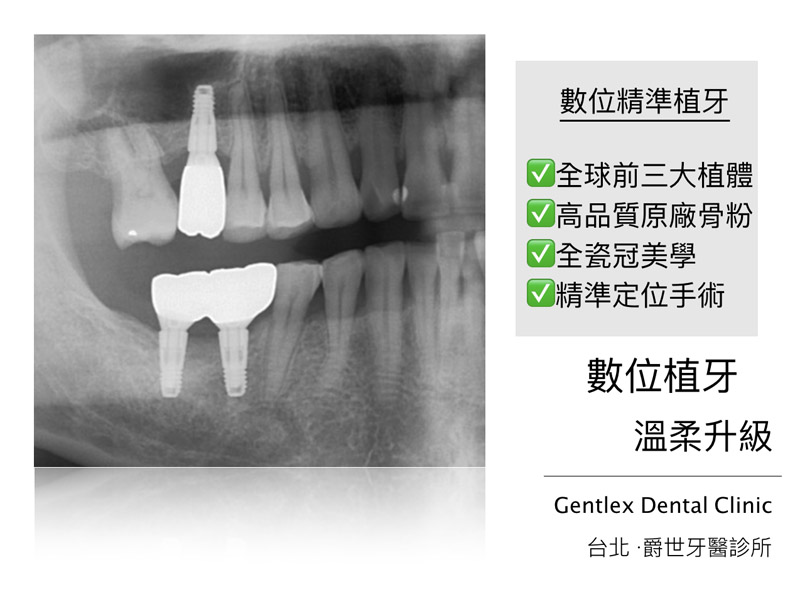

數位精準植牙

成效因人而異,必須跟從專業醫師指引

案例照片與內容均取得當事人授權同意使用,請勿私自轉載與分享